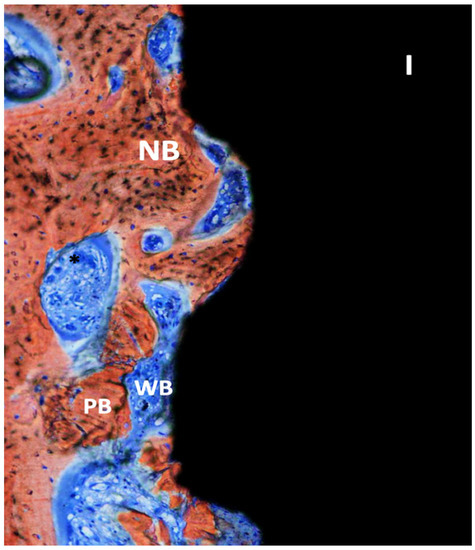

Human Histological Analysis of Early Bone Response to Immediately Loaded Narrow Dental Implants with Biphasic Calcium Phosphate® Grid-Blasted Surface Treatment: A Case Report

3. Results